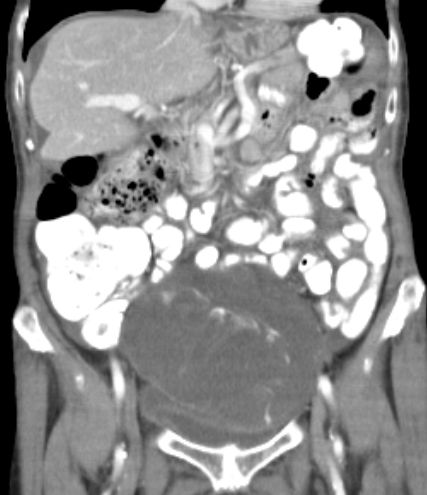

71-jährige Frau mit Adenokarzinom der Appendix pT4b pNo Mo Lo Vo.

Coloskopie: zirkuläres, exophytisch und ulzerierend wachsendes Karzinom mit einer Größe von 60 mm im Colon ascendens, nicht passierbar.![]() |

![]() |

Unmittelbar oberhalb der Ileozökalklappe Nachweis eines 7 x 6 cm großen, schüsselförmig exulzerierten Tumors.

Der Tumor durchdringt alle Wandschichten und infiltriert retrograd den davor geschalteten Dünndarm.![]() |

Ausgehend von zökumnahen Anteilen des Wurmfortsatzes,

Infiltrate eines zum Teil tubulär, zumeist kribriform und strangfrömig wachsenden malignen epithelialen Tumors.

Dieser bricht unter fibroplastischer Stromatransformation in das perimuskuläre Fettgewebe aus und infiltriert sekundär die Dünndarmwand.

CDX 2: kräftige Kernfärbung. Zytokeratin 20 z.T. gefärbt. Zytokeratin 7, Chromogranin, Synaptophysin negativ.![]() |